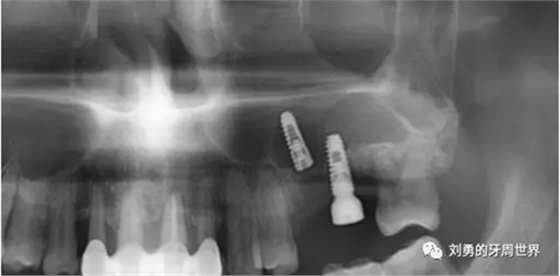

術(shù)后復查ct如下圖:

術(shù)后ct顯示種植體距離很近。植骨材料完整。